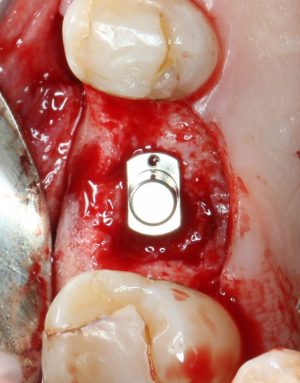

Кстати, комплект поставки не содержит ни заглушки, ни абатмента. А сам имплантат фиксируется на ключе простым заклиниванием платформы. Т. е. не слишком надёжно:

По этому поводу существует поговорка: «Кто не ронял имплантаты Astra Tech, тот не работал с имплантатами Astra Tech«. В общем, будьте аккуратны, в идеале, проводите все манипуляции по фиксации имплантата на ключе над столом.

Если лунка подготовлена правильно, то имплантат проваливается в неё почти полностью:

и докручивается до правильного положения несколькими оборотами.